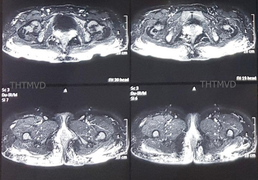

Tiêm mỡ nhân tạo để làm đẹp vòng 3 ở spa, người phụ nữ đau đớn khi vùng này bị hoại tử, phải điều trị hơn 6 tháng ở Bệnh viện Hữu nghị Việt Đức (Hà Nội) mới ổn định.